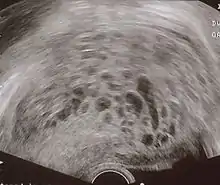

The diagnosis is strongly suggested by ultrasound (sonogram), but definitive diagnosis requires histopathological examination. On ultrasound, the mole resembles a bunch of grapes ("cluster of grapes" or "honeycombed uterus" or "snow-storm").[14] There is increased trophoblast proliferation and enlarging of the chorionic villi, and angiogenesis in the trophoblasts is impaired.[15]

Transvaginal ultrasonography showing a molar pregnancy.

Molar pregnancy in ultrasound